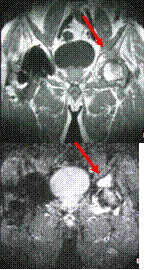

Acetabular stress fracture

Chronic hip pain